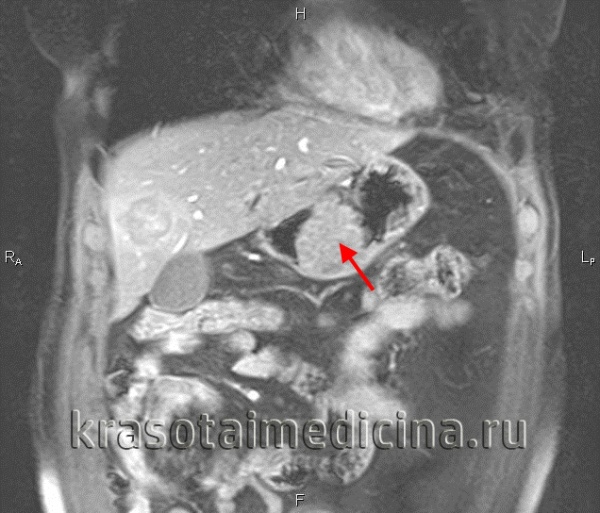

- КТ и МРТ также помогают верифицировать размеры злокачественного новообразования и его врастание в окружающие ткани, но главной целью является поиск метастазов в лимфоузлы и отдаленные органы (например, легкие).